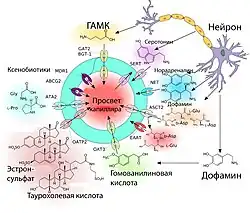

Нормальное функционирование мозга возможно лишь в условиях электролитного и биохимического гомеостаза. Колебания pH, концентрации калия в крови и других показателей не должны влиять на состояние нервной ткани. Циркулирующие в кровеносном русле нейромедиаторы не должны проникать в нервную ткань, где они могли бы изменить активность нейронов[23]. Также мозг должен быть защищён от попадания в него чужеродных агентов, таких как ксенобиотики и патогенные микроорганизмы. ГЭБ — это также и иммунологический барьер, так как он непроницаем для многих микроорганизмов, антител и лейкоцитов[26][27].

ГЭБ является также метаболическим или ферментативным (энзиматическим) барьером[6][33][34][35][36]. На поверхности клеточных мембран эндотелиальных клеток ГЭБ находится целый ряд ферментов, причём в значительно большем количестве, чем на мембранах других клеток паренхимы. Это такие ферменты, как гамма-глутамилтрансфераза и фосфатаза (в частности глюкоза-6-фосфатаза), катехол-О-метилтрансфераза, моноаминоксидаза и цитохром Р450[37][38][39]. Благодаря высокой концентрации ферментов в эндотелиальных клетках ГЭБ многие вещества метаболизируются при транспортировании через цитоплазму этих клеток[9]. Высота (размер в направлении, перпендикулярном стенке сосуда) эндотелиальной клетки ГЭБ составляет от 3 до 5 мкм (для сравнения, высота энтероцитов, эпителиальных клеток кишечника, - 17-30 мкм)[40]

Особой формой диффузии через клеточную мембрану является облегчённая диффузия. Целый ряд необходимых для мозга веществ, как например, глюкоза и многие аминокислоты, полярны и слишком велики для непосредственной диффузии через клеточную мембрану. Для них на поверхности клеточных мембран эндотелиоцитов располагаются специальные транспортные системы. Например, для глюкозы и аскорбиновой кислоты (витамина С)[139] это GLUT-1-транспортёр. Их количество на поверхности обращённой в полость сосуда в 4 раза больше, чем на обращённой к мозгу.

Кроме транспортёров глюкозы на поверхности эндотелия располагаются множество белковых молекул выполняющих подобную функцию для других веществ. Так например MCT-1 и MCT-2 ответственны за перенос лактата, пирувата, мевалоновой кислоты, бутиратов и ацетатов. SLC7 транспортирует аргинин, лизин и орнитин. В геноме мыши выявлено 307 генов отвечающих за синтез SLC-белков, ответственных за облегчённую диффузию через клеточную мембрану различных веществ[140].

Некоторые Efflux- и Influx-транспортёры являются стереоселективными, то есть переносят лишь определённый стереоизомер (энантиомер) того или иного вещества. Так например, D-изомер аспарагиновой кислоты является прекурсором N-метил-D-аспартата (NMDA), который влияет на секрецию различных гормонов: лютеинизирующего гормона, тестостерона или окситоцина[154]. L-изомеры аспарагиновой и глутаминовой кислоты являются стимулирующими аминокислотами и их избыток токсичен для ткани мозга[155]. Efflux-транспортёр ASCT2 (аланин-серин-цистеин-транспортёр) ГЭБ выводит в кровеносное русло L-изомер аспарагиновой кислоты, чьё накопление имеет токсический эффект. Необходимый для формирования NMDA D-изомер поступает в мозг с помощью других транспортных белков (EAAT, SLC1A3, SLC1A2, SLC1A6)[25][156][157].

На клеточных мембранах эндотелиоцитов располагаются также транспортёры анионов (OAT и OATP)[160][161]. Большое количество Efflux-транспортёров выводят из эндотелиоцитов целый ряд веществ в кровеносное русло[120].